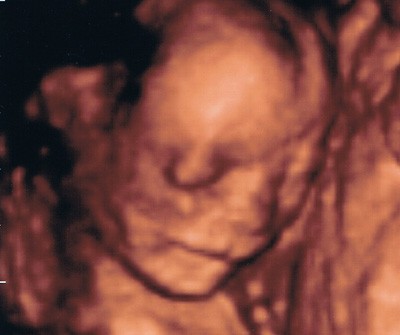

Ale ogólnie takze mnie dzis cos pobolewalo ze wzielam no-spe:-(chcialabym jutro na tym pikniku zrobic te usg,juz nawet nie wazna plec,tylko najwazniejsze zeby dzidzia sie ruszala i byla zdrowa;-)i obawiam sie tego najbardziej ,i dlatego M zostawiam w domu niech sobie spi po nocce a ja jade z koleznka i jej 2,5 letnim synkiem na Pola Mokotowskie,obawiam sie tych kolejek , ale o 11 wyjazd wiec mysle ze 11.30 bede:-)

później usłyszałam, że łożysko mimo wszystko mam nisko osadzone, w okolicach wyjścia UW a później nieśmiało zapytałam czy może już da się sprawdzić płeć dziecka no i lekarz żartowniś zapytał czy wystarczy mi pewność tak 50/50 to się śmieję i mówię,że to i teraz już wiem bez jego pomocy a ten mi nagle pokazuje na monitorze coś i mówi, widzisz to coś, no to ja że tak, zaraz potem zrobił mi usg dopochwowe i udało się zobaczyć już nieco lepiej i wyraźnieji okazało się ,że moja Dzidzia ma siusiaka!!

więc dołączam do kolejnych grudniówek spodziewających się Chłopczyka !! 15tydz 3 dzień- więc chyba dość szybko się udało

kolejna wizyta 5 sierpnia a do tego czasu jestem na L4, a od 7 sierpnia gin położy mnie do szpitala- tak dla zachowania pozorów, żeby ZUS się nie czepiał. no i chyba nici z moich wakacjino ale czego to się nie robi dla Maleństwa. wtedy też umówimy się na połówkowe usg już 4D!!